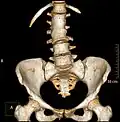

Congenital block vertebra of the lumbar spine. CT volume rendering. -

Congenital block vertebra of the lumbar spine. CT volume rendering.